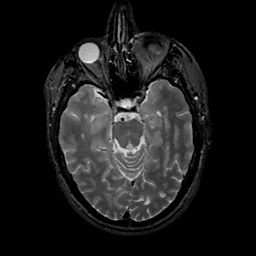

MR Study #11, May 5, 1991 -- Slice #18